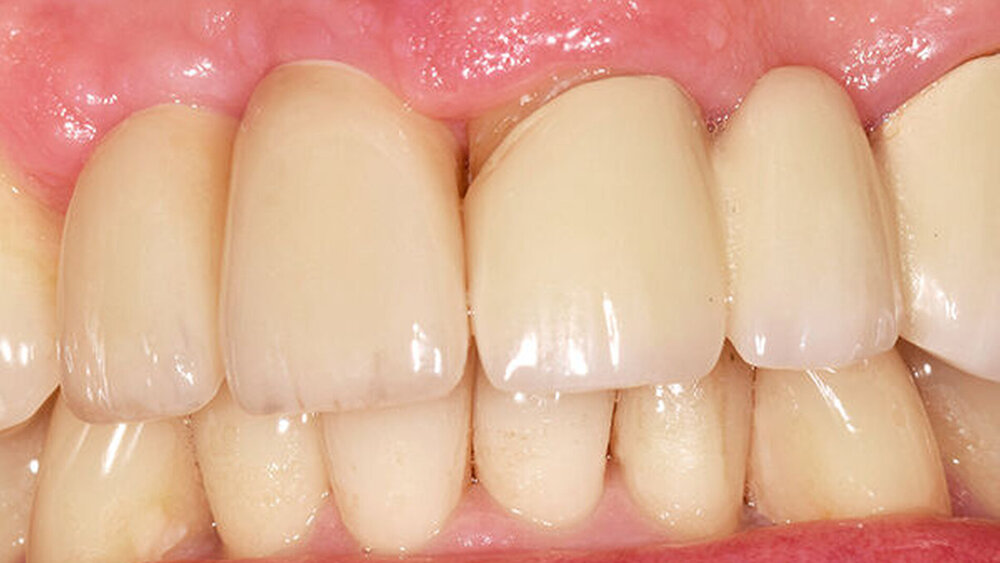

Drei Monate nach Einsetzen der definitiven Kronen erschien der Patient zur finalen Kontrolle in unserer Sprechstunde. Die keramischen Kronen (Cercon Ceram Kiss, Degudent) sind auf individuellen CAD/CAM-gefertigten Abutments (DEDICAM, CAMLOG) zementiert (Ketac Cem). Die Röntgenaufnahme zeigte osseointegrierte Implantate mit gesunder Knochenstruktur und im periimplantären Bereich keine überschüssigen Zement‧reste (Abb. 12). Die Kronen fügen sich in Form und Farbe natürlich in die Zahnreihe ein (Abb. 13). Das Emergenzprofil zwischen 13 und 12 ist aus unserer Sicht suboptimal, jedoch bei tiefer Lachlinie für den Patienten nicht relevant. Dieser ist mit seiner metallfreien Versorgung sehr zufrieden.